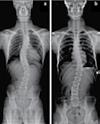

척추측만증(Scoliosis) / 척추협착증 / 허리수술 후유증

허리통증 / 허리 디스크 / 관절염 / 좌골신경통 / 고관절, 발목, 손목 통증